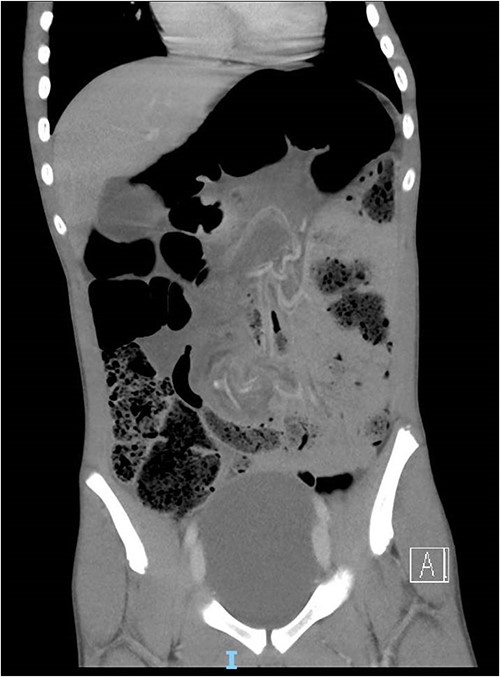

The patient presented via ambulance to a regional emergency department with diarrhoea and abdominal pain. He had a 5-day history of watery diarrhoea, intermittent cramping abdominal pain and 24 h of profuse vomiting. He had no significant medical history, developmental delay or chronic constipation. In the emergency department, the patient required methoxyflurane and multiple doses of IV morphine. He was seen by a senior paediatrician and admitted with a provisional diagnosis of bacterial gastroenteritis. Soon after admission, he became tachycardic, hypertensive and pale with a distended and hyperresonant abdomen. There was no tenderness to palpation. Plain abdominal X-ray (AXR) showed dilated loops of the large bowel (coffee-bean sign) and faecal loading throughout the ascending and descending colon suspicious for a volvulus (Fig. 1). Computed tomography (CT) demonstrated a mesenteric ‘whirl sign’ around the inferior mesenteric artery and sigmoid mesentery (Fig. 2). An emergency laparotomy revealed a sigmoid volvulus with tight twist (Fig. 3). Although viable, the sigmoid and upper rectum were resected, and a side-to-side double-stapled primary anastomosis was created. Histopathology did not demonstrate aganglionosis.

Computed tomography demonstrated a mesenteric ‘whirl sign’ around the inferior mesenteric artery and sigmoid mesentery. Dilated loops of sigmoid colon with proximal faecal loading.